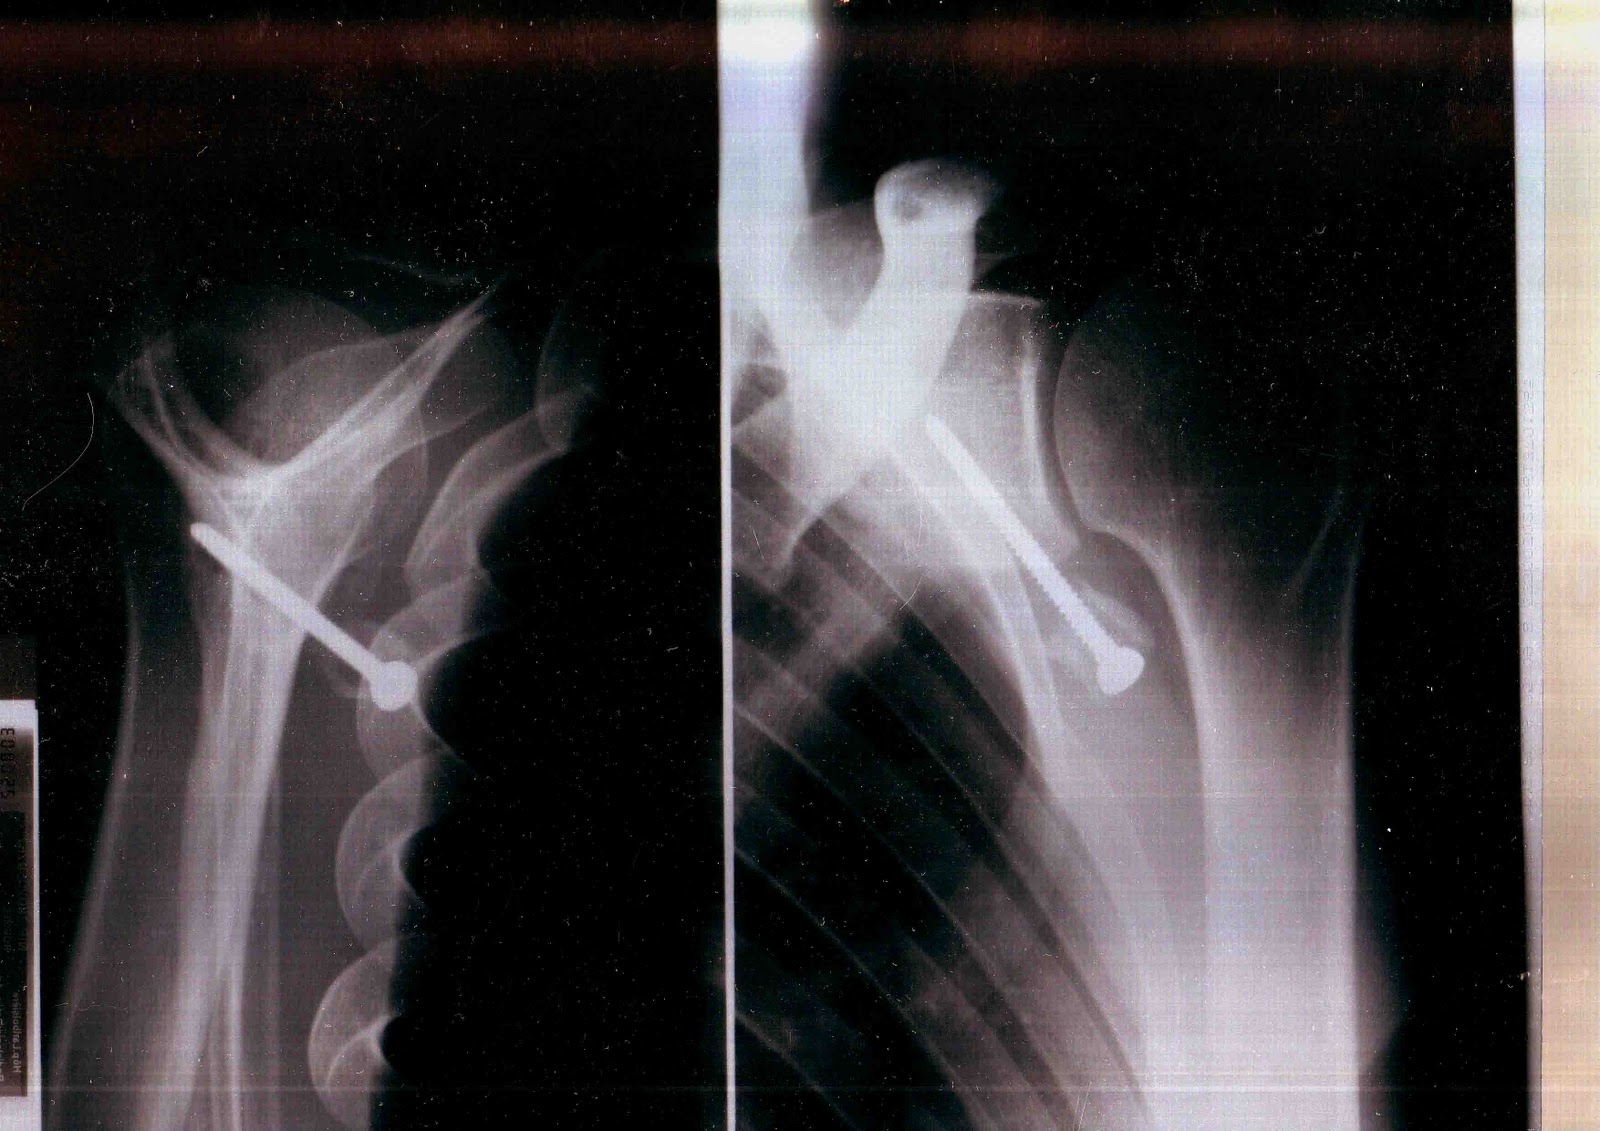

J’ ai dû me faire opérer, oh pas de grand chose, une luxation d’ épaule mais le chirurgien s’ est complètement planté, j’ étais dans un sale état quand enfin j’ ai rencontré un médecin disposé à m’ aider, on me l’ avait bien caché, il a cependant dû me réopérer trois fois.

Les hôpitaux publics me redirigeaient toujours vers l’ établissement qui m’ a raté, le service concerné prétendait que tout allait bien, que la greffe n’ avait pas prise mais qu’ elle ne bougeait pas ( examen réalisé au papier calque). Je repartais avec des ordonnances contre la douleur de plus en plus gonflées, un jour on m’ a demandé si c’ était pour un cheval lorsque j’ ai voulu reproduire l’ une d’ elles.

J’ ai tenté de porter plainte contre l’ hôpital, il parait que ça ne se fait pas, ça m’ a coûté des nerfs et pas mal d’ argent pour des rapports qui informent que la greffe était mal positionné, qu’ elle ne pouvait pas prendre mais que l’ on ne peut cependant pas considérer qu’ il s’ agit d’ une erreur. De quoi s’ agit t’ il alors ? D’ une expérience ? Est ce que j’ ai servi de cobaye ? Je n’ en saurai jamais plus, le dernier expert m’ a conseillé d’ abandonner, que j’ allais me noyer dans cette affaire.